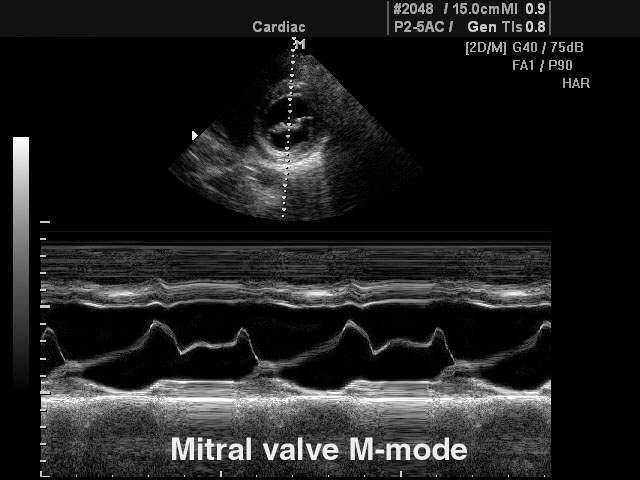

Обычный М-режим (M-mode).